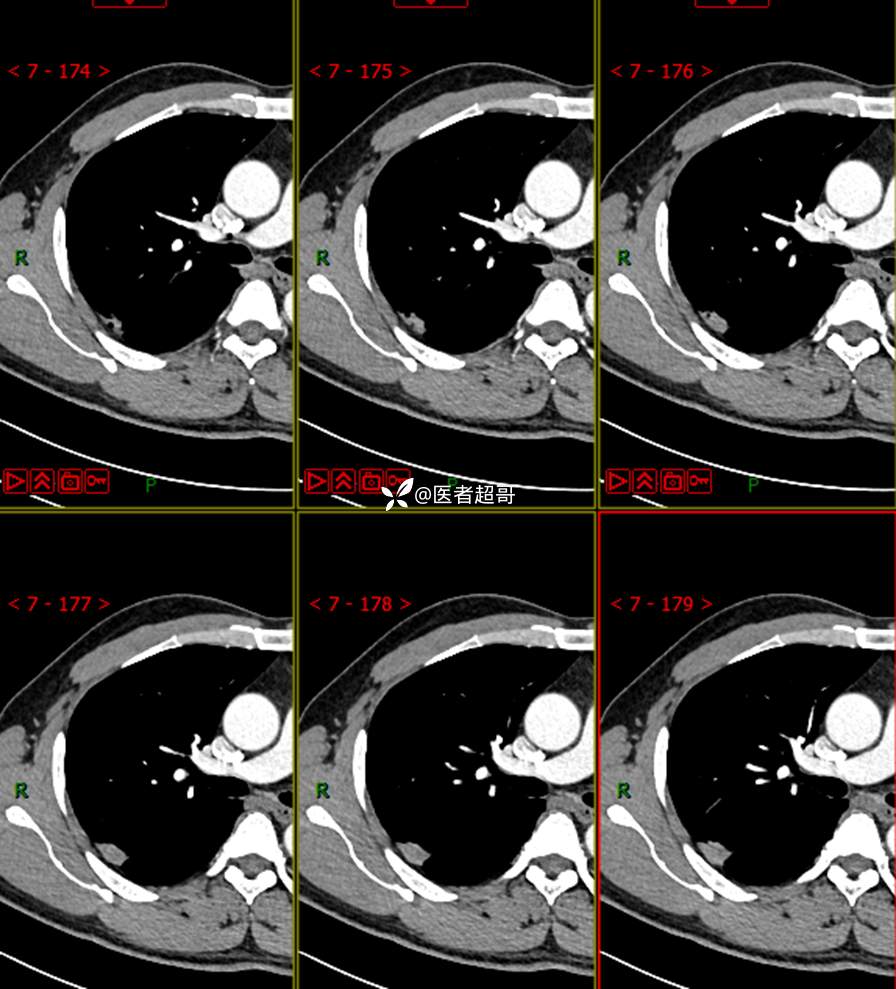

现病史:患者1年余前于体健中心行胸部X片发现右上肺叶密度增高影,无明显咳嗽,咳痰,无痰中带血及咯血,无胸痛及胸闷、气短,无发热、盗汗及全身乏力。无头痛、头晕,无腹痛、腹胀及恶心、呕吐,无声音嘶哑及呛咳,未行特殊治疗。后患者定期复查胸部CT,未见明显变化。2023-2-6患者于我院复查胸部CT:右肺上叶、下叶交接处胸膜下见实性结节影,最大截面约2.6cm×1.4cm,较前增大,建议行手术治疗。今为求进一步诊治,遂来我院就诊,门诊以“肺肿物”收入我院,患者自发病以来,神志清,精神可,饮食可,睡眠良好,大小便正常,近期体重未见明显增减。